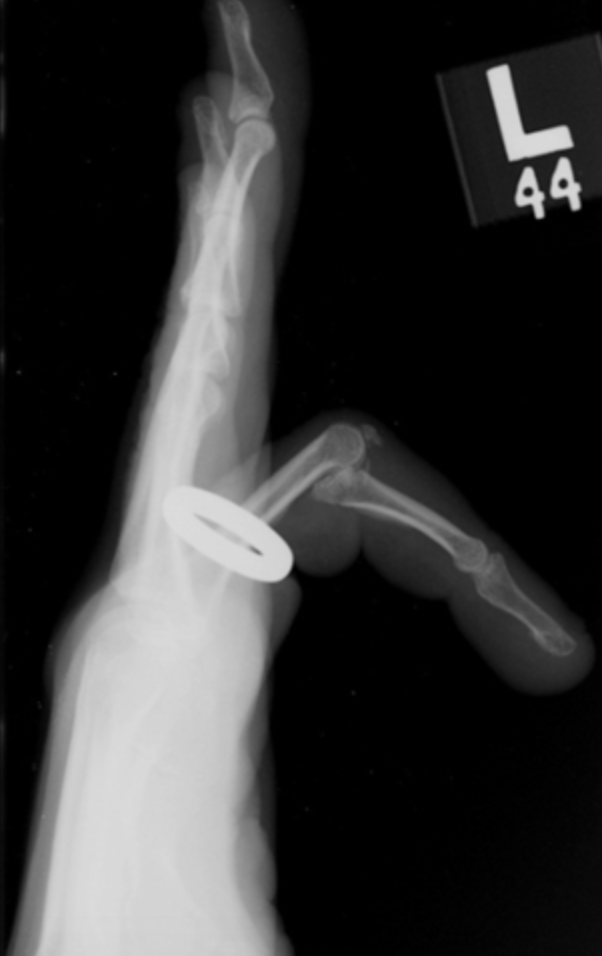

There are three types of PIP dislocations

- Dorsal (most common): The middle phalanx is displaced towards the back of the hand. (Remember dislocations are described by convention by where the distal part of the injury is in relation to the proximal part of the injury).

2. Volar: The middle phalanx is displaced towards the palm of the hand.

3. Lateral: The middle phalanx is displaced to the side.